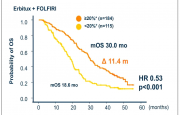

| 16:13, 27 במאי 2013 | Folfiri.png (קובץ) |  |

91 קילו־בייטים | Motyk | 1 | |